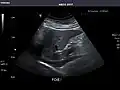

Right kidney -